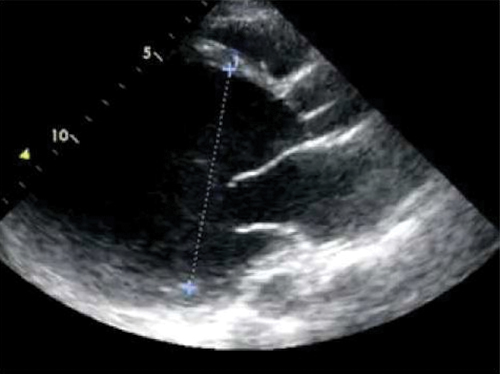

But the decisive consideration is the transthoracic ultrasound that will highlight the expansion / alteration of systolic left ventricular function, segmental contractility diameters of other cavities, valvular alterations and also assess the diastolic function of the left ventricle. Given the prothrombotic state connected with the pregnancy, the reduction in contractility, this echocardiography will seek to carefully search for the presence of thrombus intracavitary.